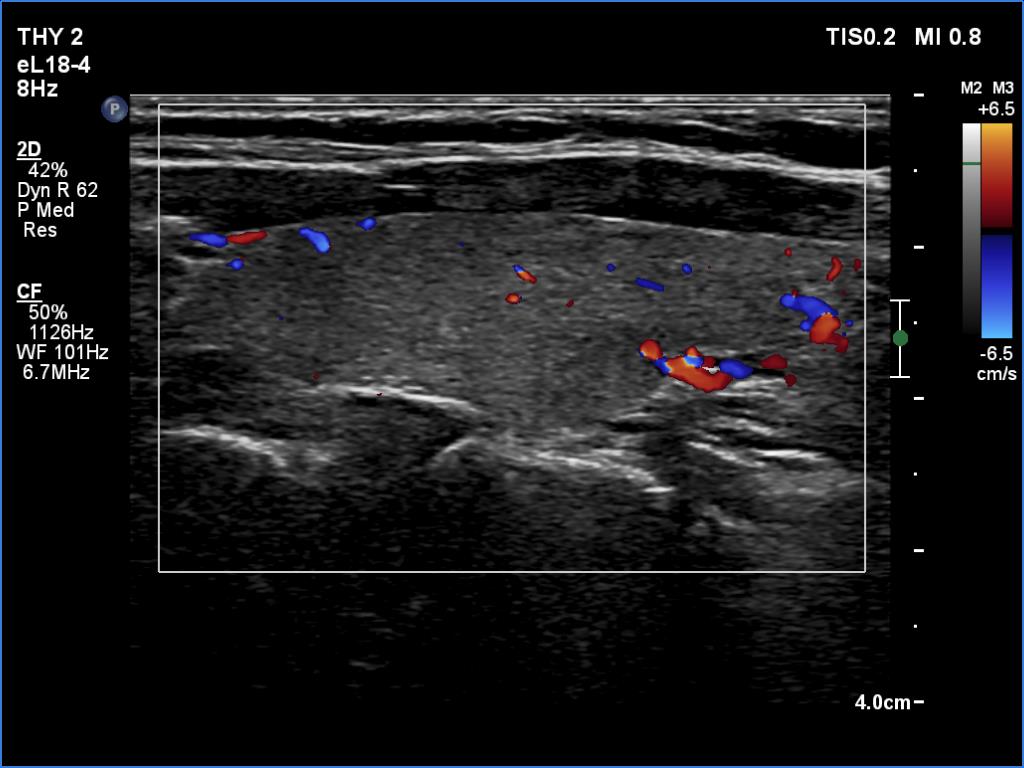

Left lobe, longitudinal scan, color Doppler mode. The vascularity is average.